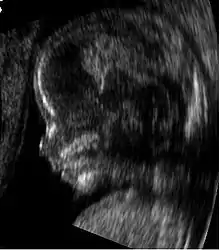

Medical ultrasound is an ultrasound-based diagnostic medical imaging technique used to visualize muscles, tendons, and many internal organs to capture their size, structure and any pathological lesions with real time tomographic images. Ultrasound has been used by radiologists and sonographers to image the human body for at least 50 years and has become a widely used diagnostic tool. The technology is relatively inexpensive and portable, especially when compared with other techniques, such as magnetic resonance imaging (MRI) and computed tomography (CT). Ultrasound is also used to visualize fetuses during routine and emergency prenatal care. Such diagnostic applications used during pregnancy are referred to as obstetric sonography. As currently applied in the medical field, properly performed ultrasound poses no known risks to the patient.[29] Sonography does not use ionizing radiation, and the power levels used for imaging are too low to cause adverse heating or pressure effects in tissue.[30][31] Although the long-term effects due to ultrasound exposure at diagnostic intensity are still unknown,[32] currently most doctors feel that the benefits to patients outweigh the risks.[33] The ALARA (As Low As Reasonably Achievable) principle has been advocated for an ultrasound examination – that is, keeping the scanning time and power settings as low as possible but consistent with diagnostic imaging – and that by that principle nonmedical uses, which by definition are not necessary, are actively discouraged.[34]

Ultrasound is also increasingly being used in trauma and first aid cases, with emergency ultrasound becoming a staple of most EMT response teams. Furthermore, ultrasound is used in remote diagnosis cases where teleconsultation is required, such as scientific experiments in space or mobile sports team diagnosis.[35]

According to RadiologyInfo,[36] ultrasounds are useful in the detection of pelvic abnormalities and can involve techniques known as abdominal (transabdominal) ultrasound, vaginal (transvaginal or endovaginal) ultrasound in women, and also rectal (transrectal) ultrasound in men.